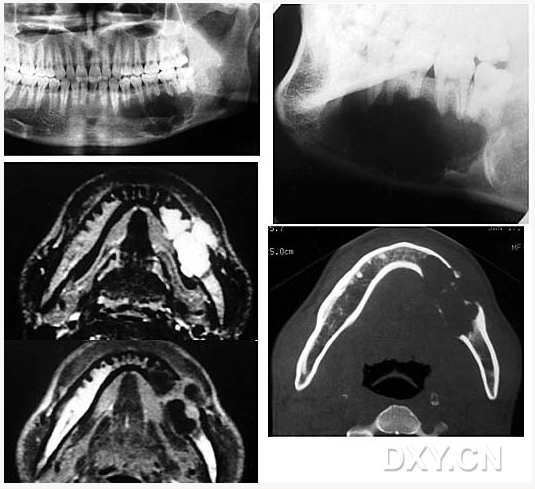

成釉細胞瘤

涎石病